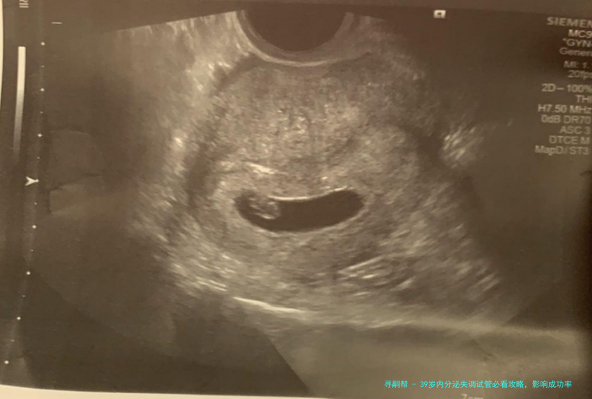

3、子宫环境

子宫环境对胚胎着床至关重要。子宫内膜厚薄程度、形态以及是否存在炎症或肌瘤等等问题,都会影响成功率。关于有子宫问题的女性,医生可能会建议进行宫腔镜检查或治疗,以改善子宫环境,提高着床率。